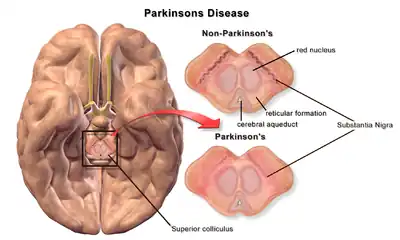

Most Parkinson's disease cases are sporadic, though contributing factors have been identified. Pathophysiology involves progressive degeneration of nerve cells in the substantia nigra, a midbrain region that provides dopamine to the basal ganglia, a system involved in voluntary motor control. The cause of this cell death is poorly understood but involves the aggregation of alpha-synuclein into Lewy bodies within neurons. Other potential factors involve genetic and environmental influences, medications, lifestyle, and prior health conditions.

Parkinson's disease (PD) is a neurodegenerative disease affecting both the central and peripheral nervous systems, characterized by the loss of dopamine-producing neurons in the substantia nigra region of the brain.[5] It is classified as a synucleinopathy due to the abnormal accumulation of the protein alpha-synuclein, which aggregates into Lewy bodies within affected neurons.[6]

Parkinson's disease has two hallmark pathophysiological processes: the abnormal aggregation of alpha-synuclein that leads to Lewy pathology, and the degeneration of dopaminergic neurons in the substantia nigra pars compacta.[97][98] The death of these neurons reduces available dopamine in the striatum, which in turn affects circuits controlling movement in the basal ganglia.[98] By the time motor symptoms appear, 50–80 percent of all dopaminergic neurons in the substantia nigra have degenerated.[98]

However, cell death and Lewy pathology are not limited to the substantia nigra.[99] The six-stage Braak system holds that alpha-synuclein pathology begins in the olfactory bulb or outside the central nervous system in the enteric nervous system before ascending the brain stem.[100] In the third Braak stage, Lewy body pathology appears in the substantia nigra,[100] and, by the sixth step, Lewy pathology has spread to the limbic and neocortical regions.[101] Although Braak staging offers a strong basis for PD progression, the Lewy pathology around 50 percent patients do not adhere to the predicted model.[102] Indeed, Lewy pathology is highly variable and may be entirely absent in some PD patients.[99][103]